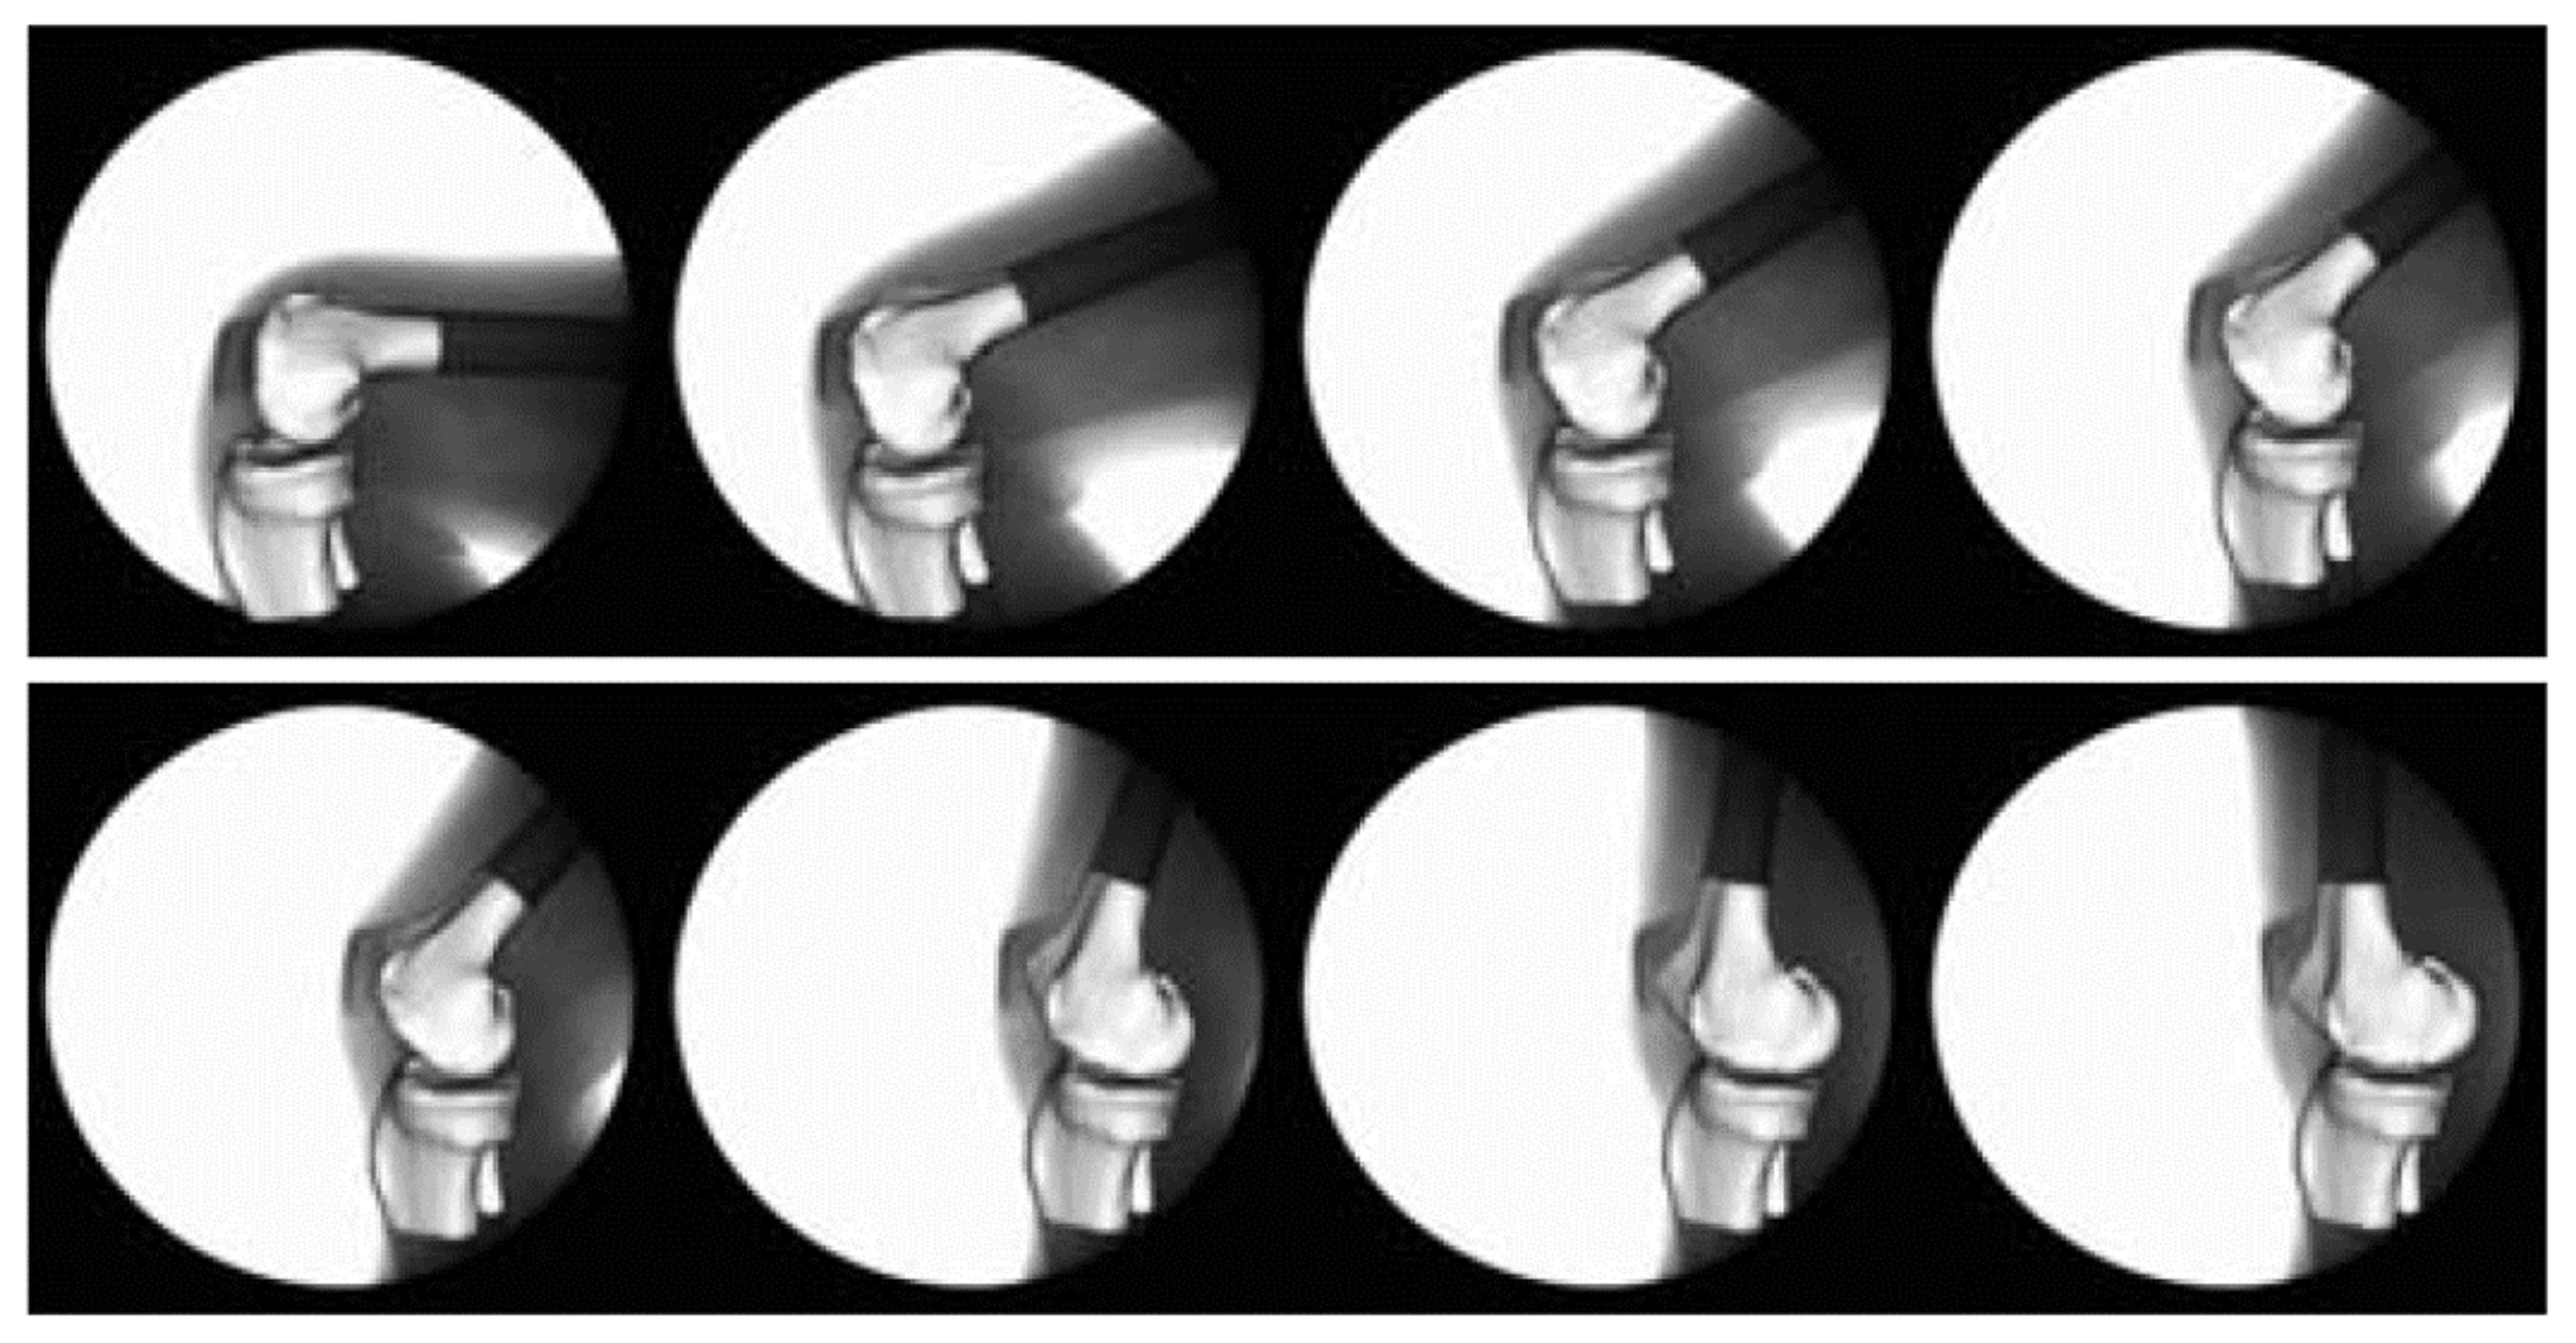

Patellofemoral pain (PFP) is the most frequent cause of knee pain. It frequently occurs in teenagers, manual labourers, and athletes. Patellofemoral pain syndrome may be caused by overuse, injury, excess weight, a kneecap that is not aligned correctly (patellar tracking disorder), or changes under the kneecap. Many researchers have shown that PFP is a precursor to early osteoarthritis [1,2], the leading cause of disability in the North American elderly population. Despite considerable efforts to improve the effectiveness of treatment interventions, 70% of individuals with PFP had persistent or recurrent symptoms 5–20 years after the intervention. Current interventions’ poor long-term outcomes highlight the necessity of better understanding the causes of PFP and its contributing factors. Generally speaking, patellar misalignment resulting in abnormal stress distribution is considered the primary mechanism for PFP [3,4]. However, the exact cause is unknown. This is due to the inability to evaluate in vivo three-dimensional (3D) patellofemoral joint (PFJ) motion during dynamic activities. Motion tracking in clinical studies is commonly based on surface marker video motion analysis, which suffers from measurement inaccuracy produced by soft tissue artefacts [5]. Therefore, researchers are investigating PFJ kinematics using 3D imaging modalities instead. In a paper by Esfandiarpour et al. [6], a new technique for real-time tracking of the knee bone structure using fluoroscopic imaging was proposed and tested. The methodology combined a computed tomography (CT) scan and bi-planar fluoroscopy techniques (see Figure 1a) to examine the knee motion with six degrees of freedom during the squatting of individuals with the syndrome and without. The calibration target shown in Figure 1b was used to correct the geometric distortion of the fluoroscopic images and determine the two imagers’ relative projection geometries. The calibration target was placed close to each image intensifier. A calibration algorithm compensated for radial distortions by using a matrix of small stainless steel spheres located at known positions, as shown in Figure 1c. Each image intensifier was independently corrected by using a radial distortion model. Then, an orientation plate (Figure 1d) was placed in the shared image acquisition area and imaged with two fluoroscopic sensors. One can compute the imaging sensors’ relative positions and orientations using the two images. Tracking the relative positions and orientations of the bones in a knee (tibia, femur, and patella) over time requires that a set of 3D mesh templates (one for each bone) must be extracted from CT imaging and individually segmented by using a simple thresholding technique (see Figure 2). One must track the projected image into the two by-plane fluoroscopic sensors to compute each knee bone’s position and orientation relative to the X-ray source (see Figure 3). Knowing the projective transform between the X-ray source and the two sensors from calibration, one can then infer what position and orientation each bone must have to produce these two images. The fluoroscopic imaging system captured two X-ray videos of the knee bones during motion from orthogonal viewpoints; one can see the resulting video sequence in Figure 4. Using an iterative re-projection software from Innomotion, Inc. (Shanghai, China) (http://www.innomotion.biz/ (accessed on 20 June 2022)) called FluoMotion, one can infer the three bones’ positions and orientations from the two orthogonal fluoroscopic image sequences. In Figure 5, one can see the projection of the knee bones for one frame, and in Figure 6, one can see a block diagram of the 3D-to-2D registration algorithm used, which is very similar to the algorithm described in [7].

Figure 4. Example of 3D knee templates re-projected into the fluoroscopic image sequence.

Diagnostics 12 02228 g004

Figure 5. Example of a 3D knee template re-projected into one fluoroscopic image. The red color correspond to the tibia, the green color to the femur, and the blue color to the patella.

Diagnostics 12 02228 g005